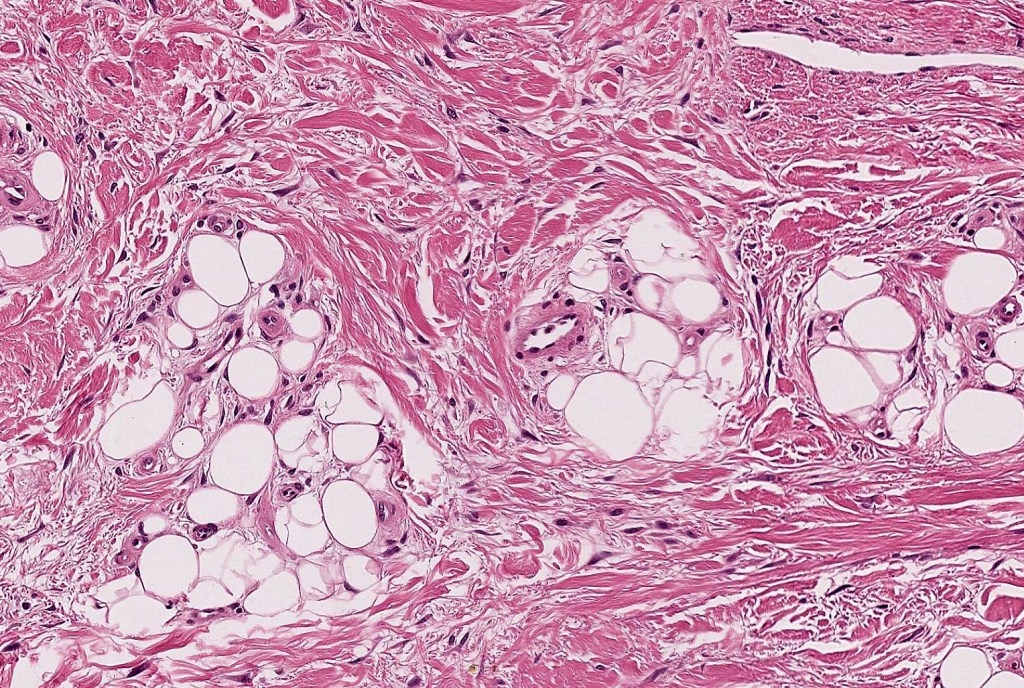

•An infundibular cyst is surrounded by laminated dermal collagen, elastic fibers, blood vessels, adipocytes & spindle cells separated from the adjacent dermis by a retraction artifact

•Exceptionally may show spindle cell lipoma-like features